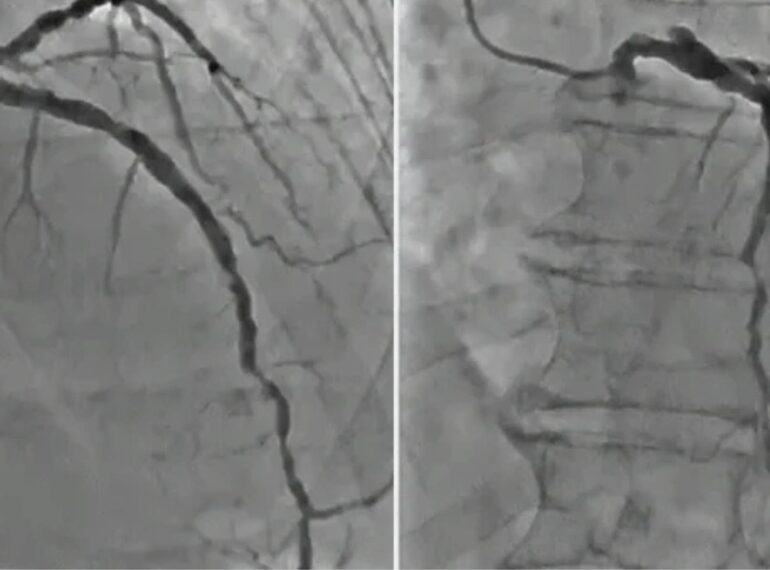

From primary angioplasty to complex stenting, receive expert treatment using the latest transradial techniques.

Coronary Angiography

Dr. Honey Sharma provides advanced hospital-based cardiac care using the latest techniques and technologies. From angioplasties to device implantations, each procedure is handled with precision and compassion by a super-specialized expert in interventional cardiology.

Radial angioplasty offers faster recovery, less discomfort, and a lower risk of bleeding compared to traditional groin access.